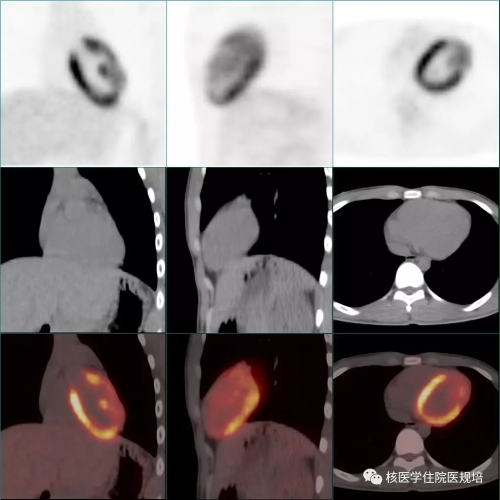

18F-FDG PET/CT显像见:左室前侧壁显影形态失常,MR所示占位相应部位与周围正常心肌组织对比呈不均匀FDG摄取减低区(SUVmax6.4),但肿物边界观察不清,相当于乳头肌处见点状FDG高摄取(图4);双侧腋窝区域分别可见一FDG摄取轻度增高(SUVmax1.8)的小淋巴结,对称性分布,淋巴结均呈长椭圆形,短径均小于1.0cm,内可见脂肪密度的门样结构(图5);另于左侧臀部下方皮下脂肪层内可见一点状FDG摄取增高灶(SUVmax6.1),相应部位CT见一边界较清晰的软组织密度结节影(图6,追问病史该结节已存在3年,局部无红肿热痛,大小始终无著变。全身其余部位未见明显异常结构改变及FDG摄取。

隔日再次行胸部 FDG PET/CT显像。显像前连续两餐进食低碳水化合物、高脂食物(第一餐为2只猪手,第二餐为5个茶叶蛋),第二餐4h后开始显像。与前次显像对照,除肿物显影外,左室其余心肌未见明显FDG摄取;前侧壁至心尖处占位表现为FDG摄取增高灶(SUVmax5.3),边界较清晰,范围约4.0×2.8×4.5cm,并侵犯乳头肌(图7)。